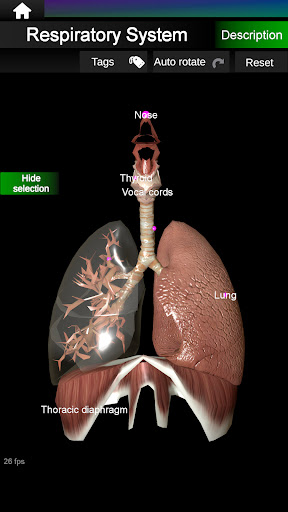

* Дихальна система, яка включає трахею, бронхи, легені та анімацію цієї системи.

* Легкий доступ і навігація (масштабування, 3D-обертання).

* Приховати або показати інформацію.

* Описи кожного органу.

* Нова опція плаваючих етикеток.